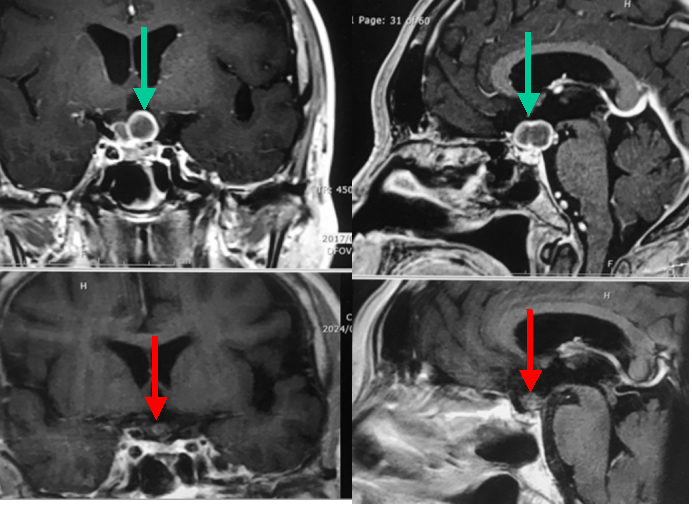

70代男性の胃がんからの多発脳転移です。上段は治療前のMRI画像で小脳に2ヶ所の腫瘍を認めます(上段の赤および緑矢印)。上段の赤矢印はともに同じ腫瘍を示しています。腫瘍が大きいためノバリスによる10分割照射を行いました。下段は4ヵ月後のMRI検査の結果です。ノバリスにより放射線治療を行った上記2つの病変は消失ないしは著明に縮小(下段赤矢印)しています。上記2病変とは別の新たな小さな転移巣ができてしまったため、これらはガンマナイフによる治療を行いました。このように当院では腫瘍の部位やサイズ等によりノバリスとガンマナイフを使い分け、もっとも適切な治療法を選択しています。

乳がん多発脳転移の患者さんです。視交叉とよばれる部位(上段左写真赤矢印)と松果体と呼ばれる部位(上段右写真赤矢印)に腫瘍があります。視神経は放射線に弱いので慎重に35Gy/10回で、松果体部は43Gy/10回での放射線治療を行いました。いずれもノバリスによる治療です。下段は1年後のMRI結果です。腫瘍はほとんどわからないまでに縮小・消失しました。幸い後遺症も生じていません。